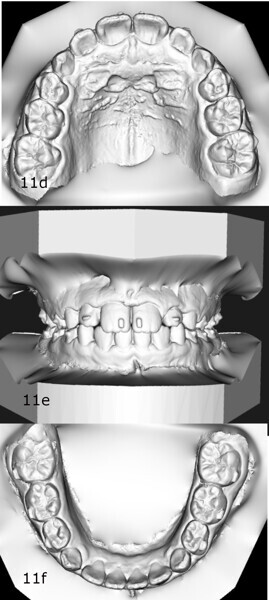

The 8-year-old male patient presented with a diastema between teeth #11 and 21 and non-eruption of teeth #12 and 22 (Fig. 1). The patient underwent a thorough orthodontic examination, including intra-oral photographs, extra-oral photographs, cephalometric radiography of the skull with cephalometric tracing, dental panoramic tomograms, impressions by intra-oral scanning, and functional and phonetic tests. Intra-oral examination (Fig. 2) and pattern analysis showed a Class I molar and canine relationship and contraction of the maxillary arch, displaced pre-contact between teeth #63 and 73, a 3.7 mm diastema between teeth #11 and 21, a mandibular midline deviation to the left, a maxillary midline to the right, and an open bite (−1.5 mm).

After 18 months of therapy, a case reassessment was carried out to verify that the goals had all been achieved (Fig. 8). Comparison of extra-oral photographs at the start of treatment (T0) and end of treatment (T1; Fig. 9) showed that excellent balance of the patient’s face had been achieved with a regular, symmetrical smile. Comparison of the intra-oral photographs (Fig. 10) and models (Fig. 11) also showed wider and more harmonious arch forms, closure of the anterior diastema, closure of the open bite and recentring of the mandibular midline. Excellent gingival trophism had also appeared.

Analysis of the models in Autodesk Netfabb software (Fig. 12) showed regularisation of the arches and an increase in the maxillary inter-canine diameter of 2.61 mm and in the maxillary intermolar diameter of 2.29 mm. The superimposition of the arches at T0 and T1 (Fig. 13), performed using OnyxCeph3 (Image Instruments), was very significant and showed the shift from the initial arch shape and size to a wider shape posteriorly but with significant control of the maxillary incisor area.